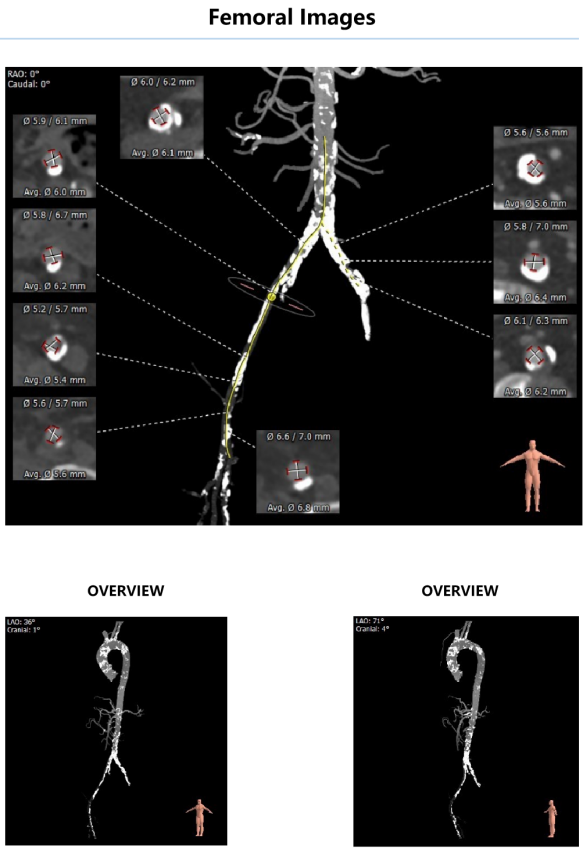

外周血管影像:

入路血管严重钙化,左髂外动脉次全闭塞病变,右髂动脉局部环状钙化,血管内径较细。

④患者腹主动脉及双侧髂股动脉多发重度钙化,左髂外动脉次全闭塞病变,右髂动脉局部环状钙化,血管内径较细,血管并发症风险较高,必要时可选择桡动脉及其他外周动脉作为入路血管。

右侧股动脉入路建立后,在双侧髂总动脉汇合处遭遇顽固钙化,器械无法向心推进,术中改以左侧腋动脉为主入路。